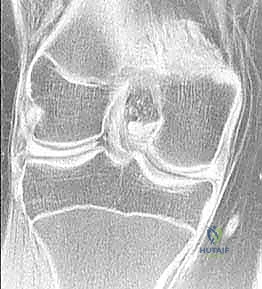

- التصوير بالرنين المغناطيسي (MRI): هو المعيار الذهبي (Gold Standard) لتشخيص تمزقات الغضروف الهلالي. يوفر صوراً ثلاثية الأبعاد وعالية الدقة للأنسجة الرخوة. من خلال الرنين، يستطيع الدكتور هطيف تحديد نوع التمزق، حجمه، موقعه (في أي منطقة دموية)، وما إذا كانت هناك إصابات مصاحبة (مثل تمزق الرباط الصليبي الأمامي ACL).